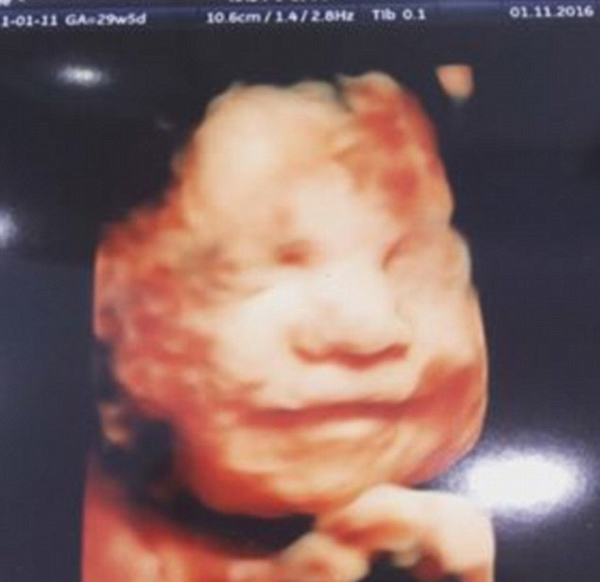

神奇的微笑!英国一胎儿4D孕检中展露笑容

据英国《每日邮报》11月3日报道,27岁的英国孕妇艾梅?费根(AimeeFagan)(已育有两个女儿)2日在利物浦的超声检查中心接受4D...[2016-11-07]